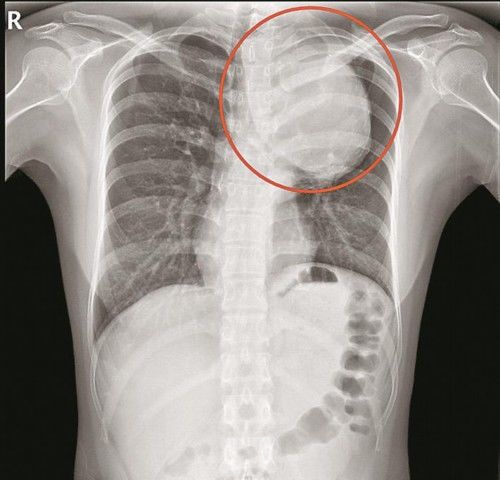

▲胸片显示动脉瘤很大

“患者的胸主动脉瘤非常大,位于主动脉弓降部,它会像吹气球一样,越长越大。正常人的主动脉弓部只有香肠那么大,而患者的主动脉瘤直径达75mm,已经有青芒那么大了,是正常人的5倍,瘤子像一条蟒蛇一样,从颈部长到膈肌,深入隐藏在患者体内。”南方医科大学深圳医院心脏与血管外科主任杨建安说。